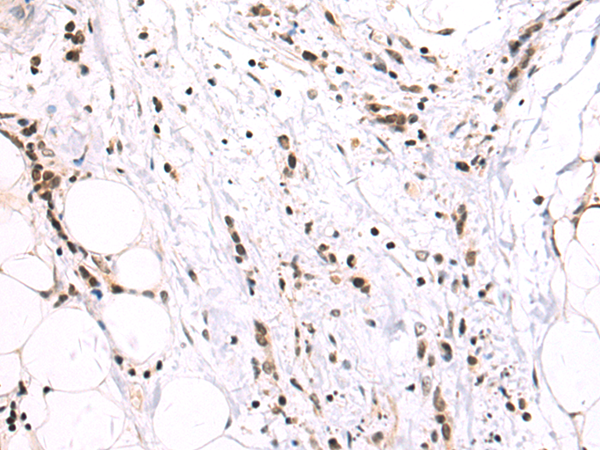

质检流程